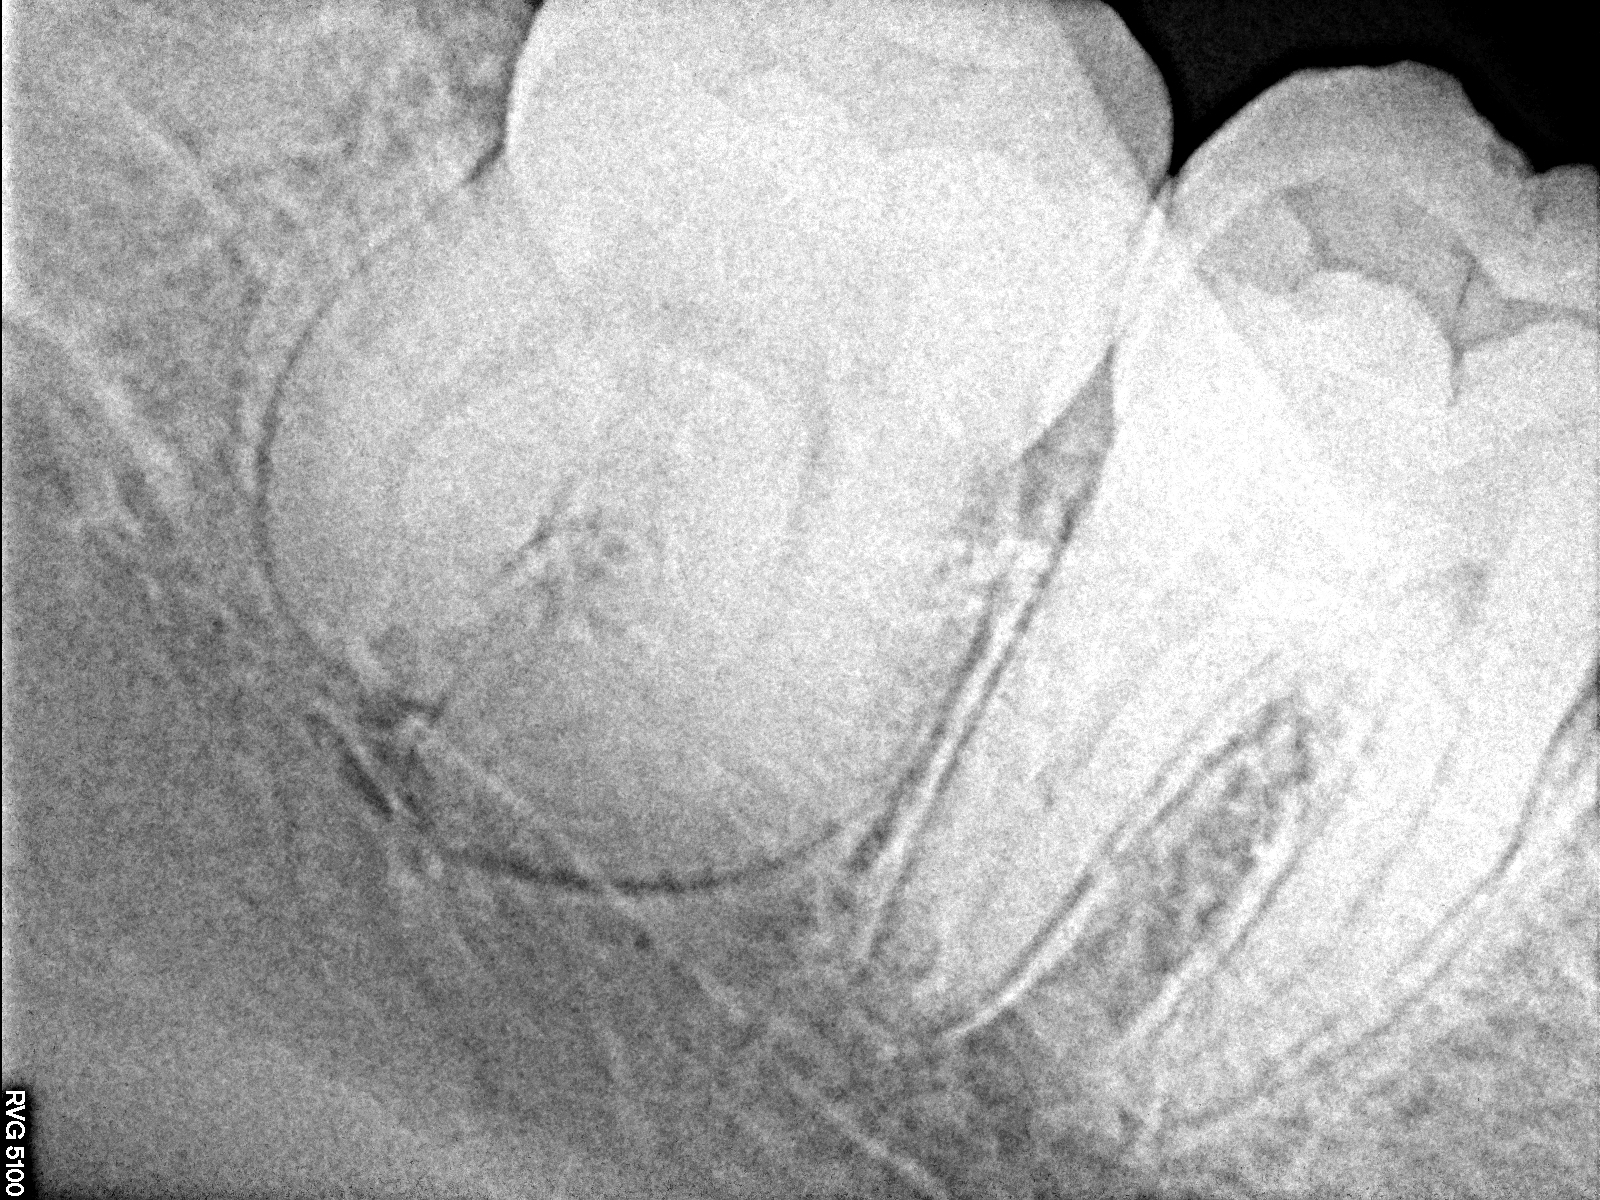

デンタルレントゲンになります

玉ねぎのように丸々と太っていました